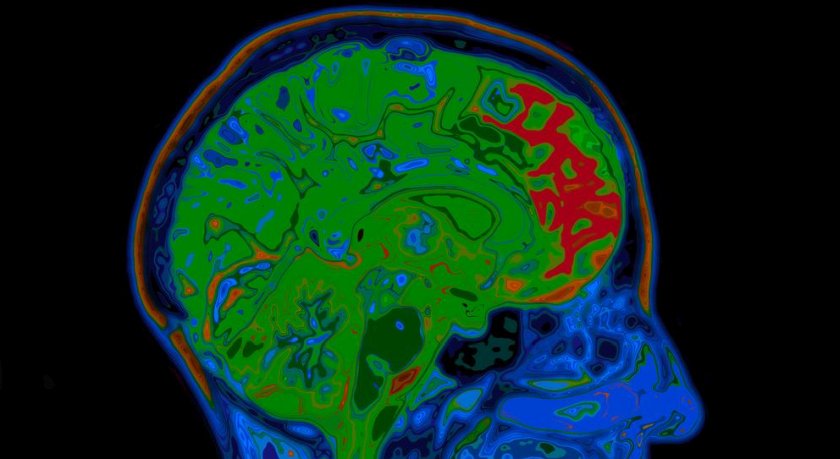

Per capire se le malattie critiche e l'infezione sono associate ai cambiamenti della struttura cerebrale alla base del declino cognitivo e della demenza, il team di ricerca ha analizzato i dati dell'Ariosclerosis Risk in Communities Study (ARIC), che comprendevano risonanze magnetiche della struttura cerebrale, oltre che informazioni sociali, demografiche e ospedaliere di una grande coorte di partecipanti seguiti in un periodo di 24 anni, che comprendeva 5 esami medici e interviste strutturate.

Per la sua analisi, il team di Walker si è concentrato su un sottogruppo di soggetti ARIC che hanno ricevuto una risonanza magnetica cerebrale durante l'esame medico finale dello studio, per esaminare l'evidenza di atrofia e danni alla cosiddetta sostanza bianca, la parte del cervello responsabile della trasmissione di messaggi.

La sostanza bianca danneggiata appare superbianca su una scansione, simile alla sovraesposizione di una foto, spiega Walker, ed è stata misurata con un programma automatico. Tutti i partecipanti che hanno ricevuto questa risonanza magnetica cerebrale sono stati inclusi nell'analisi.

Il gruppo di ricerca ha scoperto che il ricovero durante il periodo di studio, indipendentemente dal motivo, era associato a un volume di iperintensità della materia bianca maggiore del 9% e a una integrità significativamente inferiore della microstruttura della sostanza bianca.

Tra i 1.214 pazienti ospedalizzati considerati nell'analisi, quelli che avevano una o più malattie critiche avevano un volume del cervello del 3% più piccolo nelle regioni del cervello come l'ippocampo che sono implicati nel MA. L'infezione grave è stata associata a un minore volume cerebrale in regioni vulnerabili al MA (2% più piccole) e al 10% in più di volume ventricolare cerebrale.